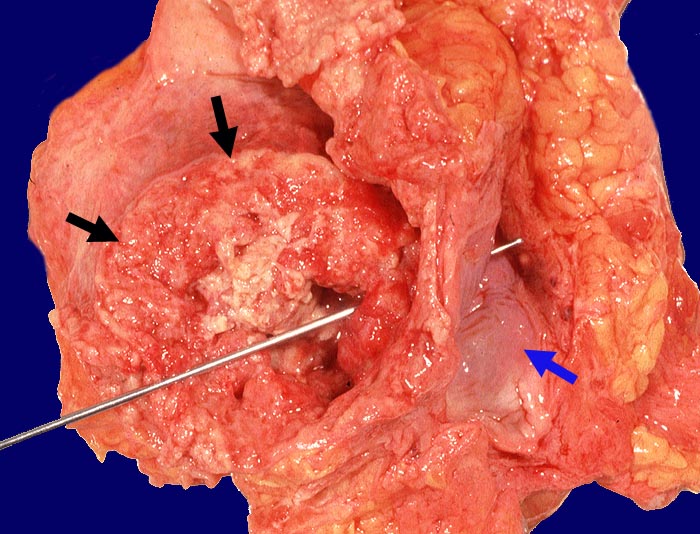

Bei den invasiven Urothelkarzinomen der Harnblase unterscheidet man nach dem Wachstumsmuster papilläre und solide Karzinome. Invasive Urothelkarzinome weisen oft deutlichen Zellatypien auf (geringer Differenzierungsgrad). Zumindest herdförmige plattenepitheliale oder adenomatöse Differenzierungen (Metaplasien) kommen oft vor und haben keine prognostische Bedeutung. Eine Ausnahme bilden kleinzellige Karzinomanteile, die die Prognose deutlich verschlechtern. Ausserhalb des invasiven Karzinoms zeigt das Urothel gehäuft ein Carcinoma in situ. (> 3629) (> 3401).

Wenn keine Metastasen vorliegen, kann ein Patient durch radikale operative Eingriffe (Zystektomie mit pelviner Lymphknotendissektion, Nephrektomie) geheilt werden. Bei inoperablen Patienten sollten eine potentiell kurative Bestrahlung oder Chemo-/Radiotherapie erhalten. Bei den primär metastasierten Urothelkarzinomen versprechen Chemotherapien einen guten palliativen Effekt.

Insgesamt ist die Prognose invasiver Karzinome schlecht. Nur 30% dieser Patienten überleben 3 Jahre. Falls eine Zystektomie durchgeführt werden kann, ist die Prognose besser (50% 5-Jahres Überleben).